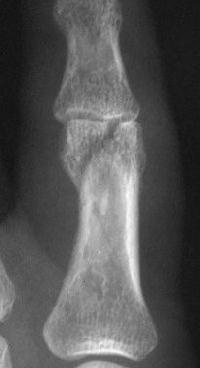

Unicondylar fractures of the phalangeal head are common, frequently unstable and unacceptably displaced. Although some may be treated successfully with percutaneous reduction and fixation, many require open reduction. In these cases, the screws were put right through the collateral ligament and sunk into the cortex. I think the simplest way to do this is to reduce and stabilize with two K wires, then remove the wires and replace with screws, one at a time, so reduction is maintained throughout. 1mm=39/1000" Kwire, so doing the math, here is how you choose the right sized Kwire to use as both drill and provisional fixation:

With two screws, bicortical fixation is not needed. The video below illustrates the steps involved, which are the same with either open or percutaneous fixation.